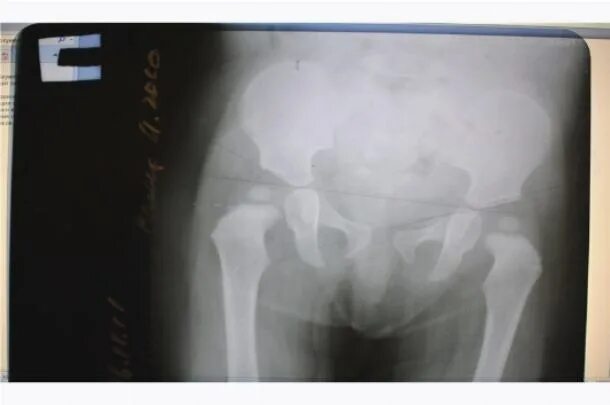

Мкб дисплазия тазобедренных суставов детей